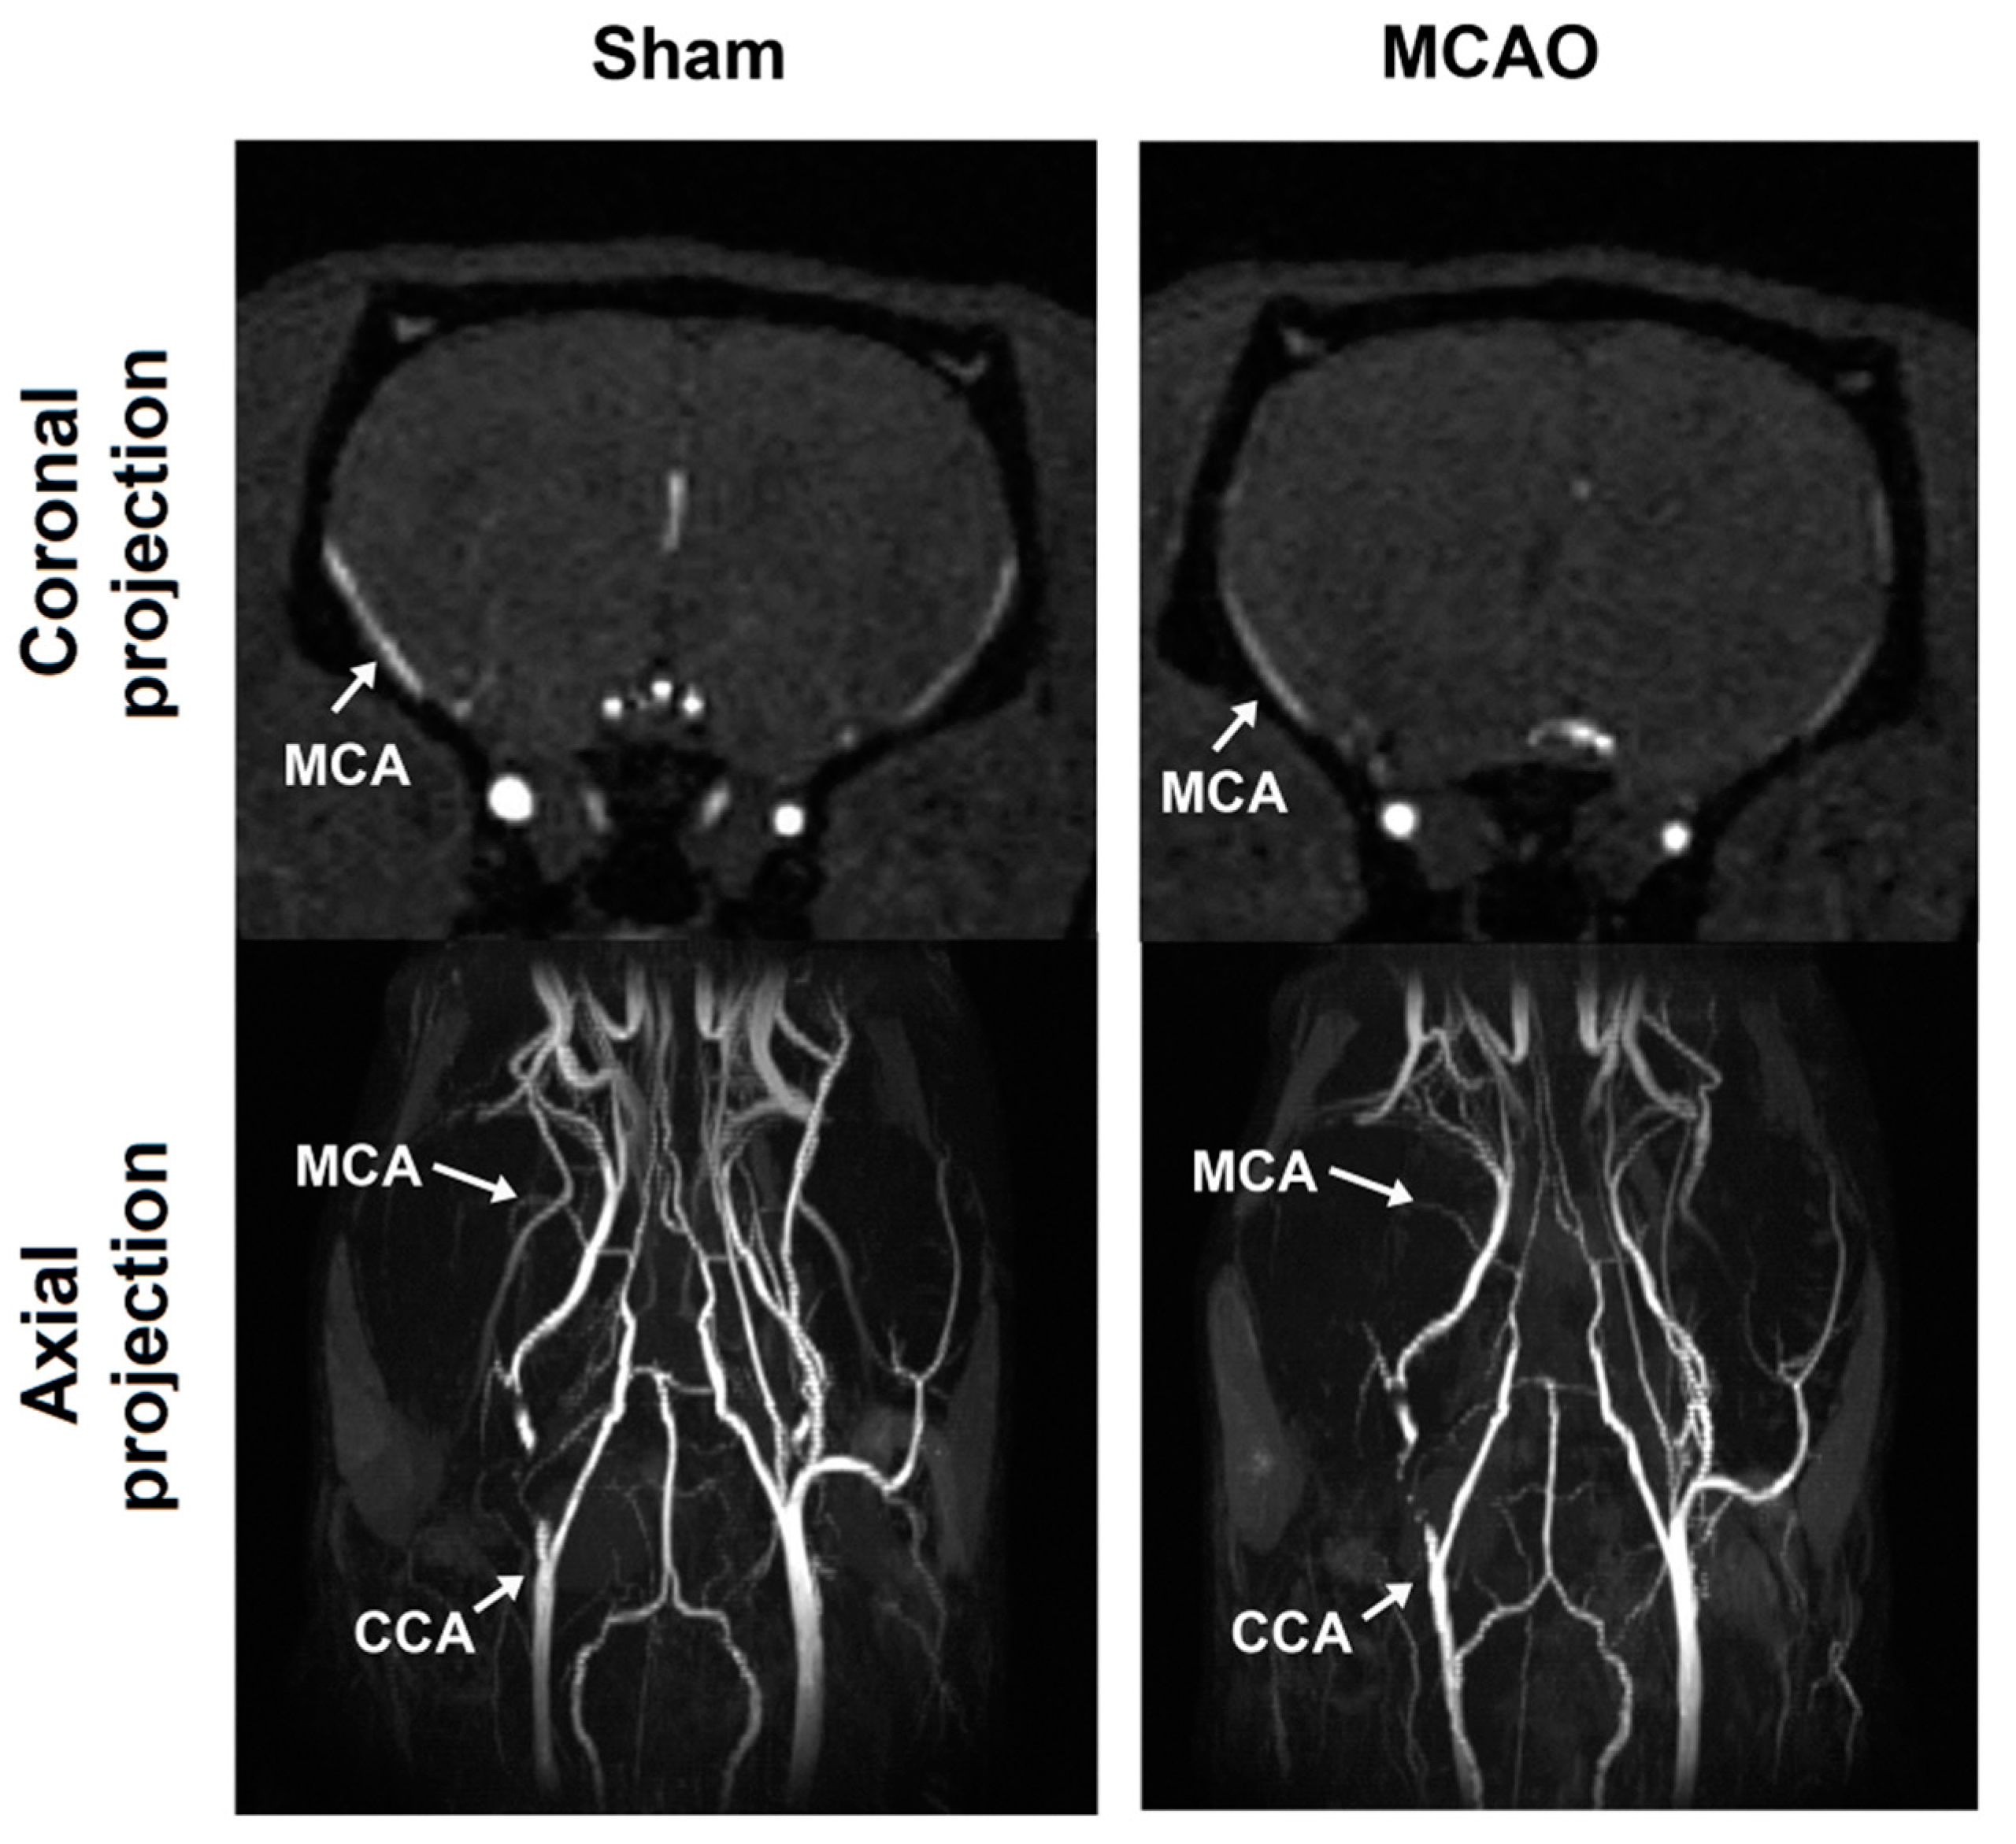

4.3. MCAO Model

| CCA | Common carotid artery |

| MCA | Middle cerebral artery |

| MCAO | Middle-cerebral-artery occlusion |

| MIP | Maximum intensity projection |